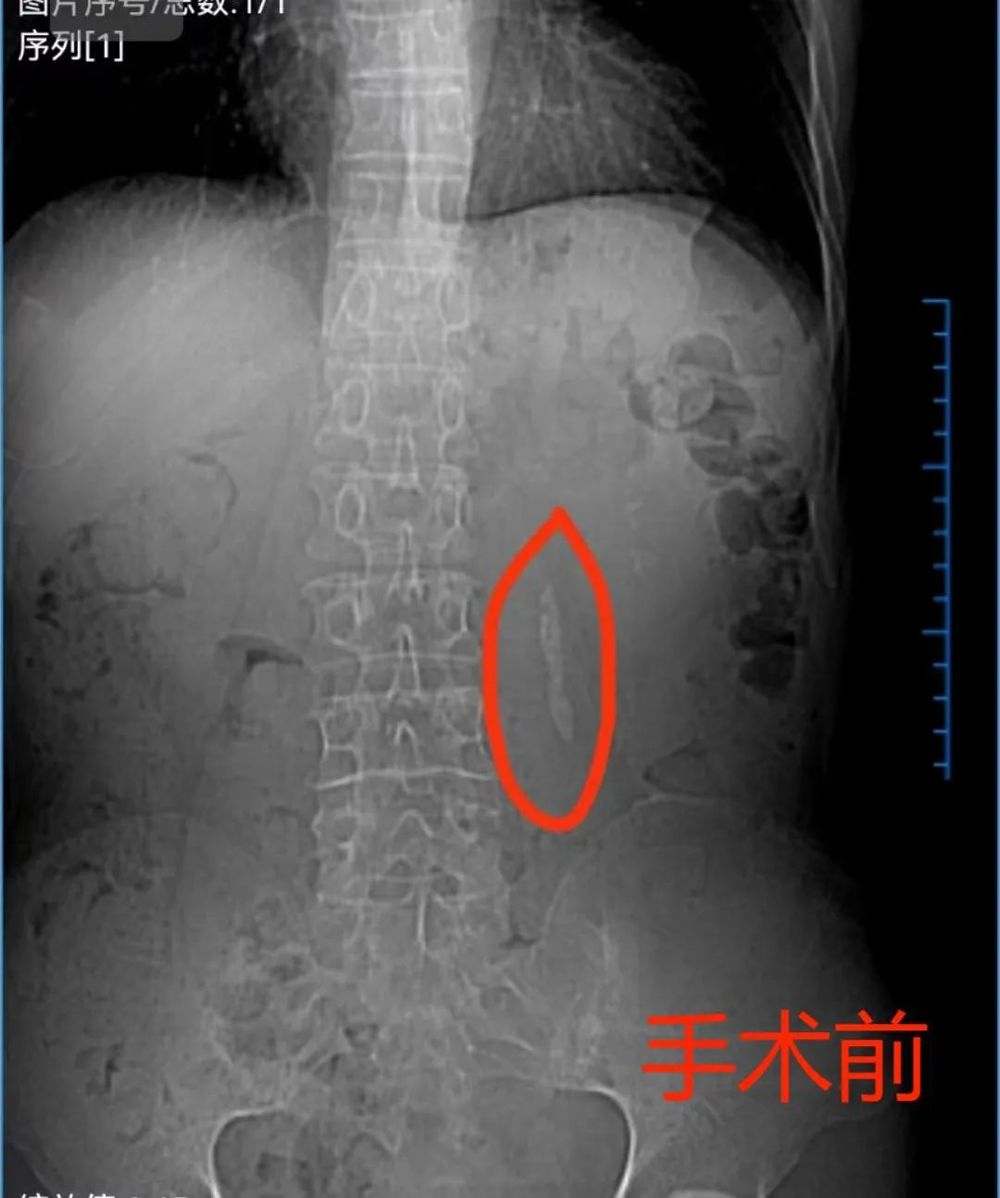

患者:黃XX,男,69歲,反複左(zuǒ)腰部脹痛5個月,2周前在門診碎石治療(liáo)後因小結石較多在排石過程中形成“石街”,入院前泌尿(niào)係彩超提示:左(zuǒ)輸尿(niào)管上端結石並擴張,左腎中度(dù)積水,左腎結石。泌尿係CT:提示左輸尿(niào)管上段結石並同側輸尿管擴張並同側腎積水,左腎(shèn)結石。2023年10月17日入院,完善術(shù)前檢查後於2023年10月20日經尿道輸尿管(guǎn)軟鏡左輸尿管結石鈥激光(guāng)碎石取石術。

手術術前術後泌尿係平片(piàn)對比: